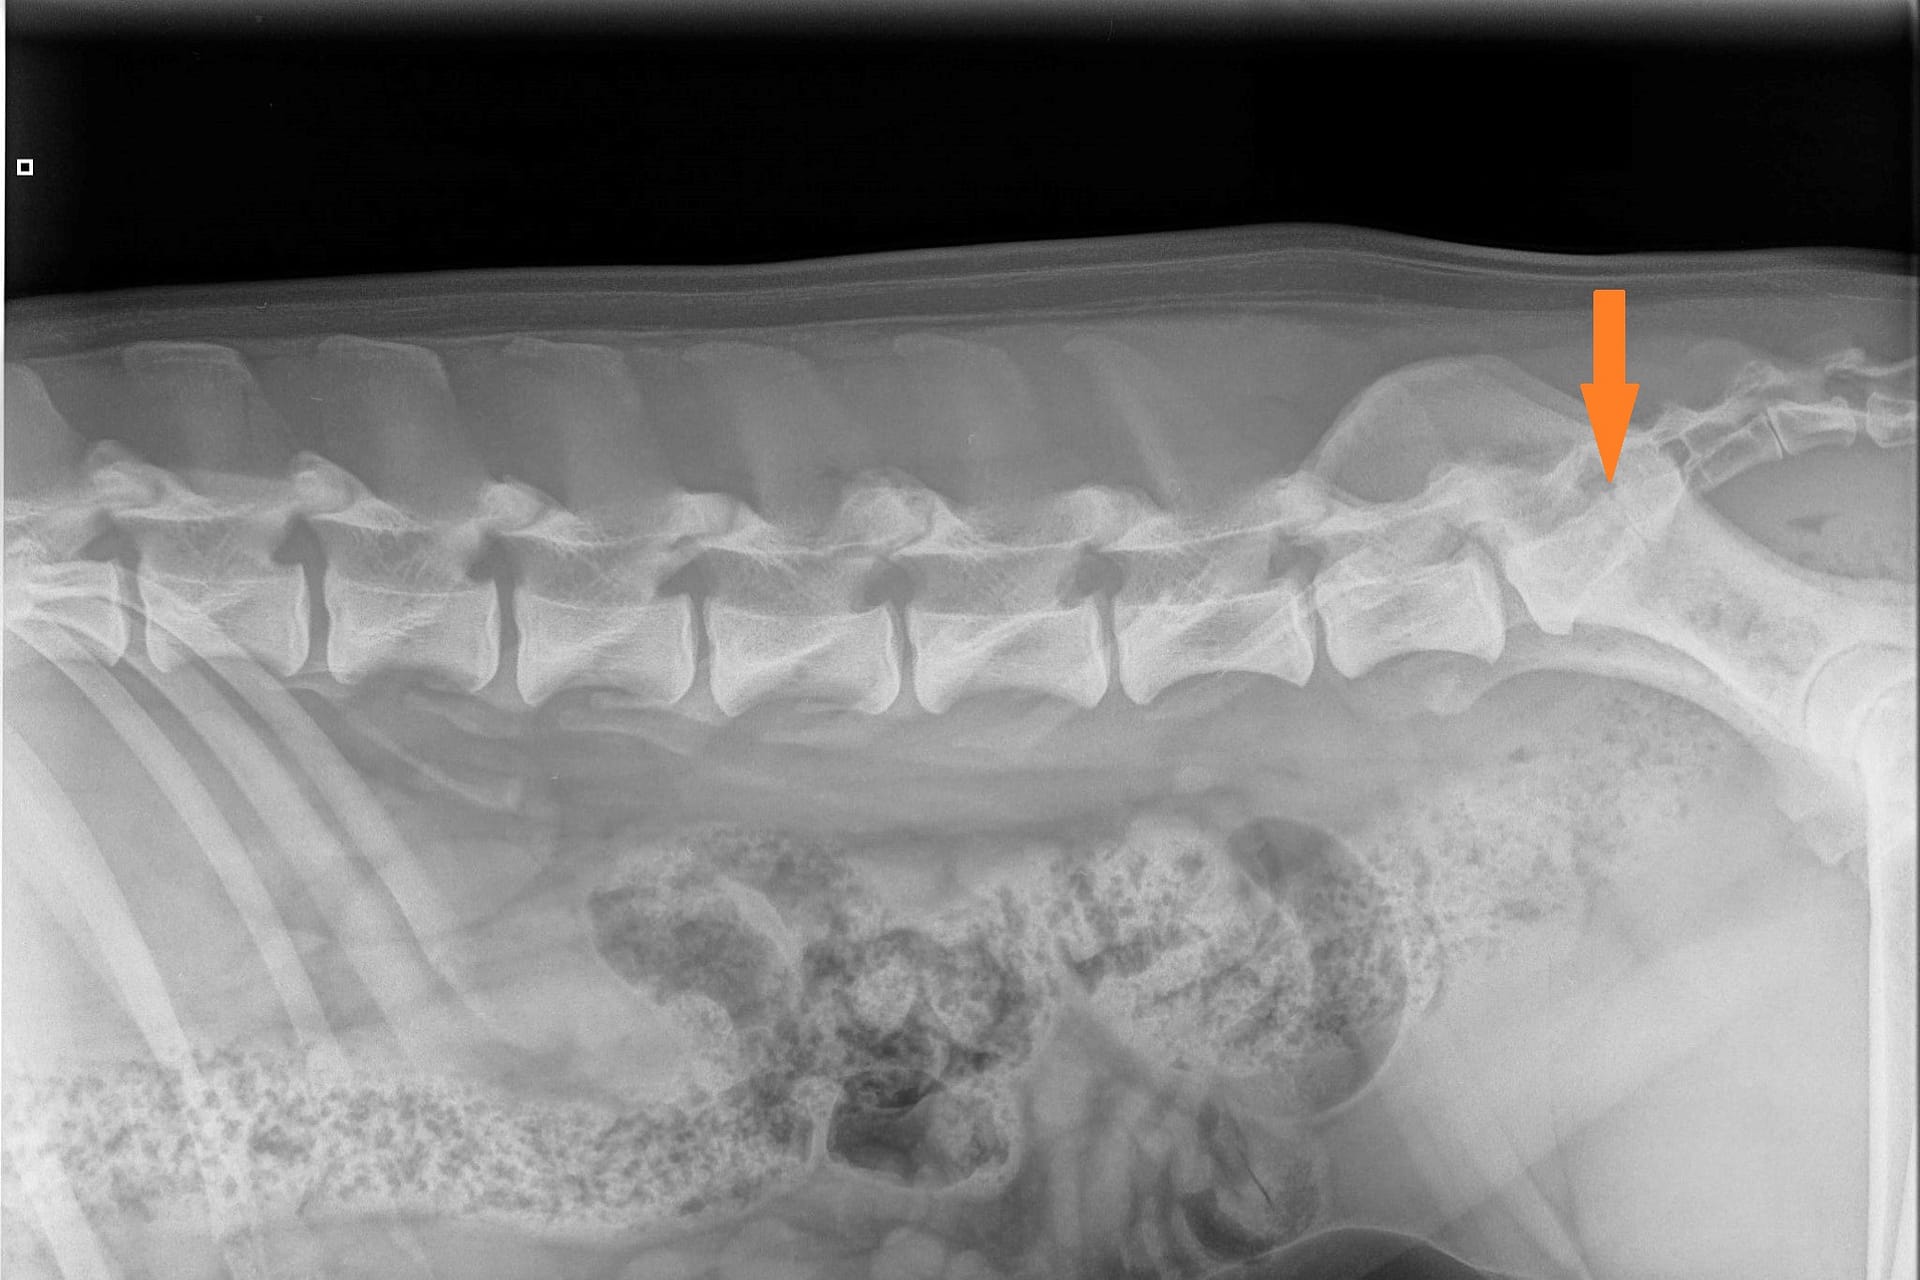

Kuvaamalla kaula-, rinta- ja lannerangan sekä ristiluun voi saada selkälausunnon LTV:stä, spondyloosista ja epämutoisista nikamista (VA). LTV- ja VA-lausunnon saa 12 kk ikäiselle koiralle ja spondyloosilausunnon 24 kk ikäiselle. Kennelliiton ohje selkärangan kuvaamiseen: https://www.kennelliitto.fi/lomakkeet/selkarangan-kuvauksen-suoritus

NORMAALI SELKÄRANKA

Koiran normaali selkäranka koostuu seitsemästä kaulanikamasta (C1-7), kolmestatoista rintanikamasta (T1-13), seitsemästä lannenikamasta (L1-7) ja kolmesta ristinikamasta (S1-3). Nikamien laskenta aloitetaan ensimmäisestä rintanikamasta (T1). Häntänikamien CD) määrä vaihtelee.

Ristiluu yhdistää lannerangan lantioon. Se on osa lantiota, joka sijoittuu lannerangan ja hännän väliin. Lonkkaluiden väliin asettuva ristiluu on vahva ja kolmiomainen muodoltaan. Normaali ristiluu koostuu kolmesta yhteenluutuneesta nikamasta; S1, S2 ja S3.